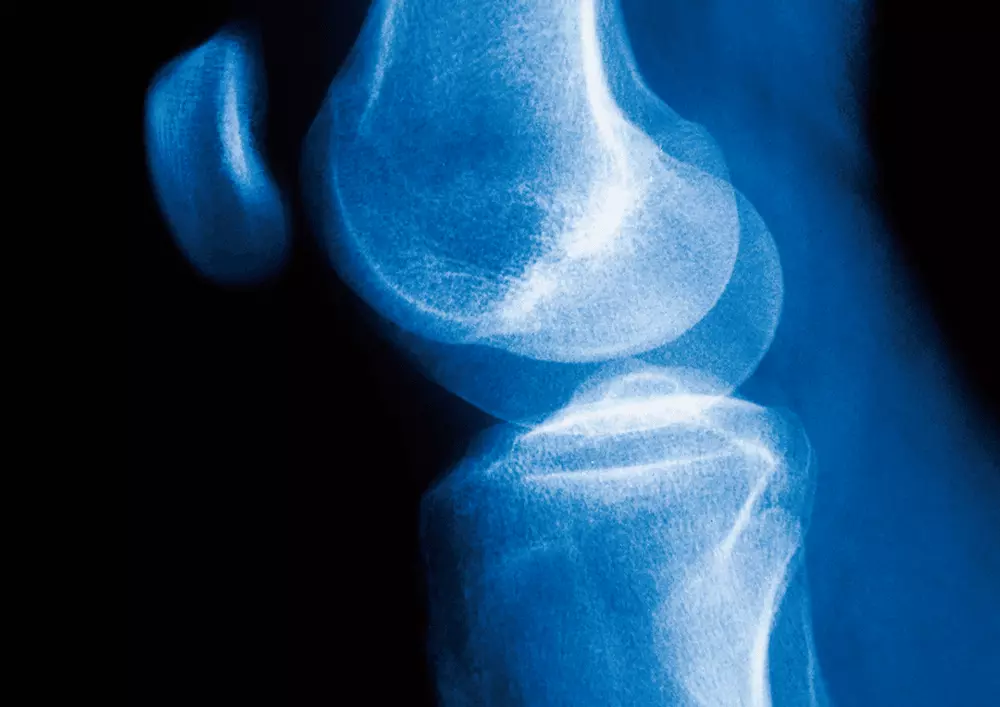

Rehabilitacja stawu kolanowego

W aktualnym numerze omawiamy również rehabilitację stawu kolanowego z patologią łąkotkową po leczeniu artroskopowym. Celem terapii fizykalnej w takim wypadku jest odzyskanie pełnej funkcji stawu oraz eliminacja bólu. Rehabilitacja stawu kolanowego z wykorzystaniem fizykoterapii oraz kinezyterapii pozwala na przyspieszone gojenie tkanek i powrót do sprawności. W artykule znajdą Państwo omówienie następujących metod: pole magnetyczne niskiej częstotliwości, laseroterapia, sonoterapia, elektrostymulacja.

Postępowanie rehabilitacyjne po implantacji łąkotki poliuretanowej

W dziale „Z praktyki gabinetu” publikujemy artykuł pt. „Postępowanie rehabilitacyjne po implantacji łąkotki poliuretanowej”. Autorka wskazuje w nim na wyjątkowość i skuteczność implantu poliuretanowego Actifit, podkreślając jednocześnie, że rehabilitacja to element procesu leczenia, opisując szczegółowy program usprawniania. Postępowanie rehabilitacyjne w takim przypadku ma wpływać m.in. na likwidację bólu, wysięku, obrzęku oraz stanu zapalnego, osiągnięcie właściwej masy, siły i kontroli mięśniowej czy reedukację czucia głębokiego pacjenta.